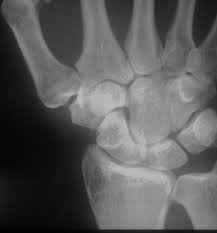

1 2 3 4 5 6. Hier ist die Radiusfraktur nicht mit einer Platte sondern mit Kirschnerdrähten erfolgt. Wenn nun diese Schrauben entfernt werden kann es passieren dass die Knochen dann keinen Halt mehr haben und auseinander oder zusammen fallen.

Gelegentlich ist es nicht möglich das Material vollständig zu entfernen so dass es auch vorkommen kann dass Reste des Metalls im Körper belassen werden müssen. Ich habe neulich das Gleiche bei einem Schrank erlebt. Die Stabilität sollte nach der Entfernung kein Problem sein weil die Schrauben und Nägel immer versetzt angeordet sind also die Löcher nie über- untereinander lägen. Die ist hart und sehr spitz und lässt sich nicht bewegen. Sollten Metallteile weggebrochen sein werden die dann auch im Knochen belassen die tun nix. Hier ist die Radiusfraktur nicht mit einer Platte sondern mit Kirschnerdrähten erfolgt. Obwohl ein Schraubenloch noch lange im Röntgenbild nachweisbar ist kommt es zu einer fortschreitenden Geflechtknochenbildung die die Stresskonzentration im Schraubenloch zunehmend herabsetzt. Hierbei wird in manchen Fällen lediglich die einzelne Stellschraube entfernt wobei die komplette Metallentfernung ungefähr nach einem Jahr beginnt. Auch nach einem Jahr kann man im Röntgenbild nach einer Schraubenentfernung die Schraubenkanäle gut erkennen.